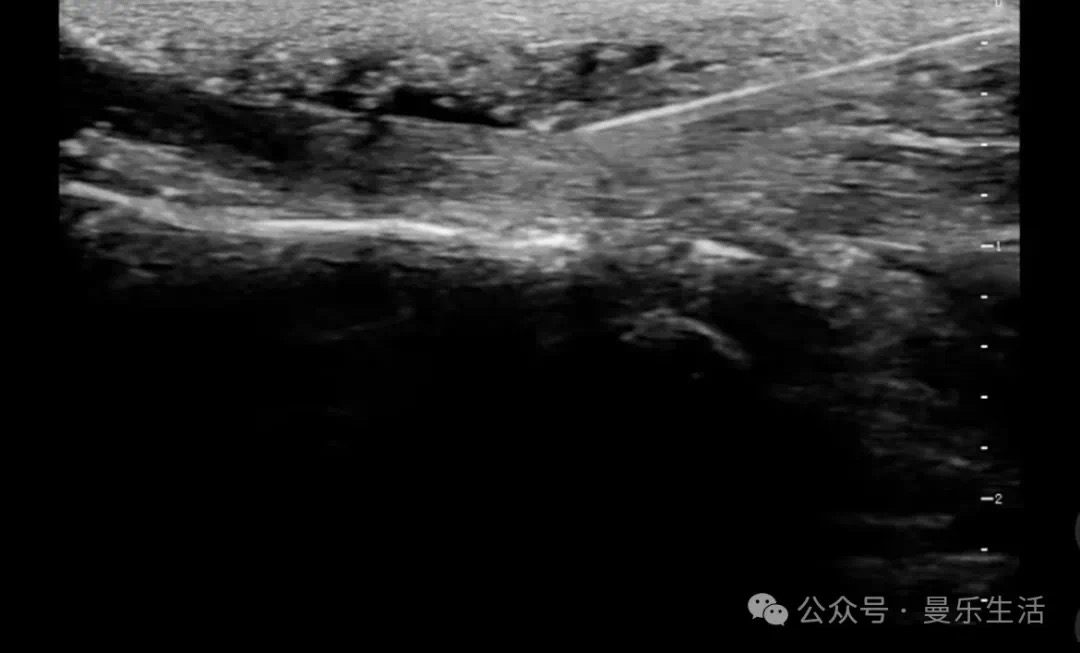

超聲引導(dǎo)下肌筋膜高糖注射技術(shù):精準(zhǔn)修復(fù)慢性疼痛的“糖水療法”??

慢性肌筋膜疼痛、關(guān)節(jié)炎癥等問題長期困擾著患者,傳統(tǒng)治療方式如藥物或手術(shù)往往存在局限性。近年來,一種名為超聲引導(dǎo)下肌筋膜高糖注射技術(shù)的創(chuàng)新療法逐漸興起,通過注射高濃度葡萄糖溶液,刺激組織再生修復(fù),成為微創(chuàng)治療領(lǐng)域的“新星”。一、技術(shù)原理:用“糖水”激活身體修復(fù)密碼該技術(shù)核心在于利用15%-25%?高滲葡萄糖溶液注射至受損筋膜、肌腱或韌帶間隙。高濃度糖分通過以下機(jī)制發(fā)揮作用:局部高滲脫水:糖水使受損組織脫水,觸發(fā)炎癥反應(yīng)。細(xì)胞募集:吸引中性粒細(xì)胞和巨噬細(xì)胞聚集,清除壞死組織。纖維再生:刺激成纖維細(xì)胞增殖,促進(jìn)膠原沉積,最終修復(fù)損傷。二、適用癥:從肩頸到足底,精準(zhǔn)“對(duì)癥下藥”技術(shù)適用于多種慢性炎癥與軟組織損傷:肌腱炎(如肩袖損傷、網(wǎng)球肘)滑膜炎(關(guān)節(jié)疼痛、腫脹)足底筋膜炎(晨起足痛)運(yùn)動(dòng)損傷后修復(fù)(肌腱撕裂、韌帶松弛)卒中后肌張力障礙(如肩關(guān)節(jié)疼痛僵硬)三、技術(shù)優(yōu)勢:超聲引導(dǎo),安全又高效精準(zhǔn)定位:超聲實(shí)時(shí)顯示筋膜、韌帶結(jié)構(gòu),避免傳統(tǒng)盲注風(fēng)險(xiǎn)。個(gè)性化方案:根據(jù)注射部位調(diào)整濃度(肌筋膜?12.5%-15%,關(guān)節(jié)腔25%)。微創(chuàng)無創(chuàng):針頭細(xì)小,幾乎無痛,術(shù)后恢復(fù)快??芍貜?fù)治療:效果不佳時(shí)可多次注射,安全性高。長期追蹤:通過超聲動(dòng)態(tài)觀察修復(fù)進(jìn)程,優(yōu)化治療方案。四、注意事項(xiàng)短期反應(yīng):約?30%?患者注射后?1-3?天疼痛可能加重,需提前溝通。聯(lián)合療法:與?PRP(富血小板血漿)結(jié)合可提升療效?30%?以上。